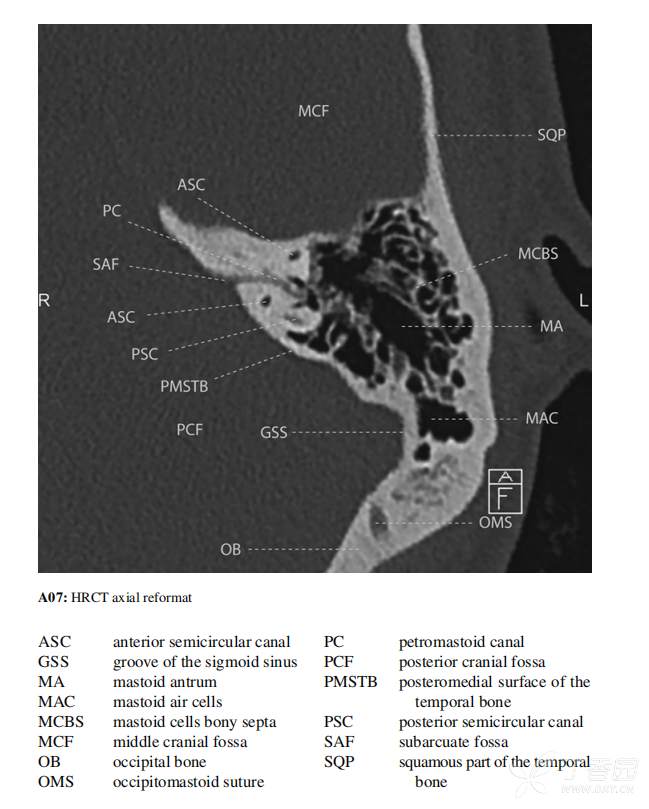

颞骨CT及MRI图像图解Temporal Bone CT and MRI Anatomy: A Guide to 3D Volumetric

附有PDF,图像质量不错,失冠轴都有,需要的下载吧,也可以留言沟通

Temporal Bone CT and MRI Anatomy ( PDFDrive ).pdf (48.2 MB)